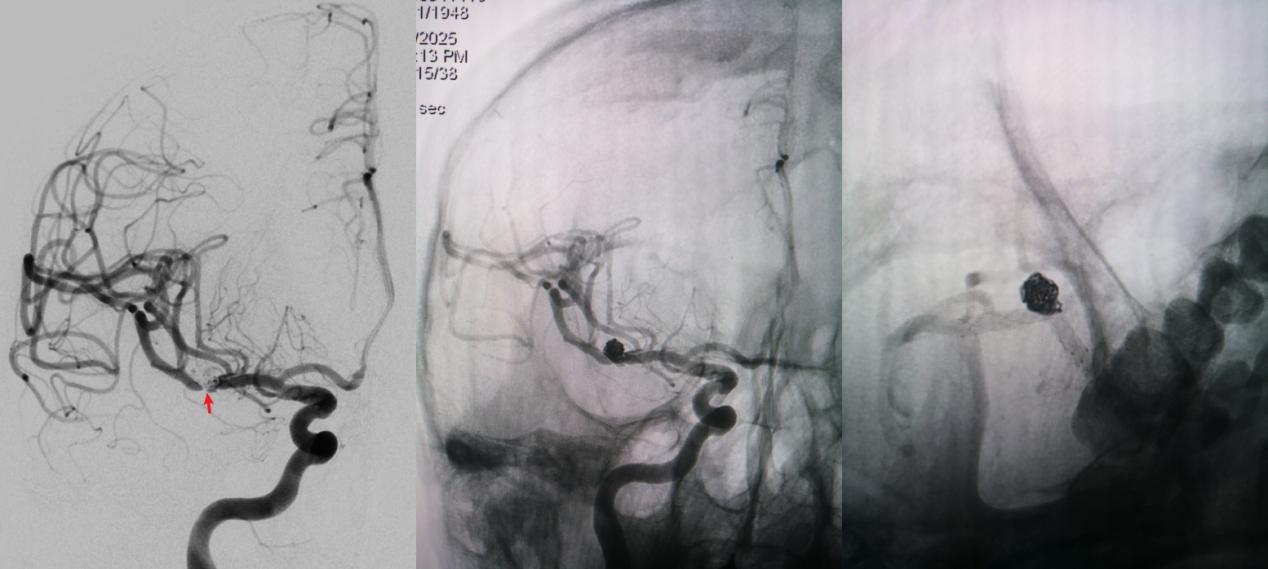

病例二为58岁女性患者。因“突发剧烈头痛伴呕吐3小时”就诊于清华大学附属垂杨柳医院急诊科,行头颅CT检查提示蛛网膜下腔出血。患者嗜睡,频繁呕吐,不排除颅内再出血。为争分夺秒抢救患者生命,神经外科脑血管病介入团队紧急为患者实施了DSA,显示左侧大脑中动脉分叉处宽颈动脉瘤,主要累及下干。术中采取双微导管技术,于动脉瘤内填塞弹簧圈,并置入一枚支架保证致密栓塞和下干分支血管的通畅。成功“拆弹”,化险为夷,患者恢复过程顺利,出院时无神经功能缺损。

▲术前DSA显示左侧大脑中动脉分叉宽颈动脉瘤,可见子瘤,主要累及下干

▲术后DSA显示动脉瘤致密栓塞,载瘤动脉通畅